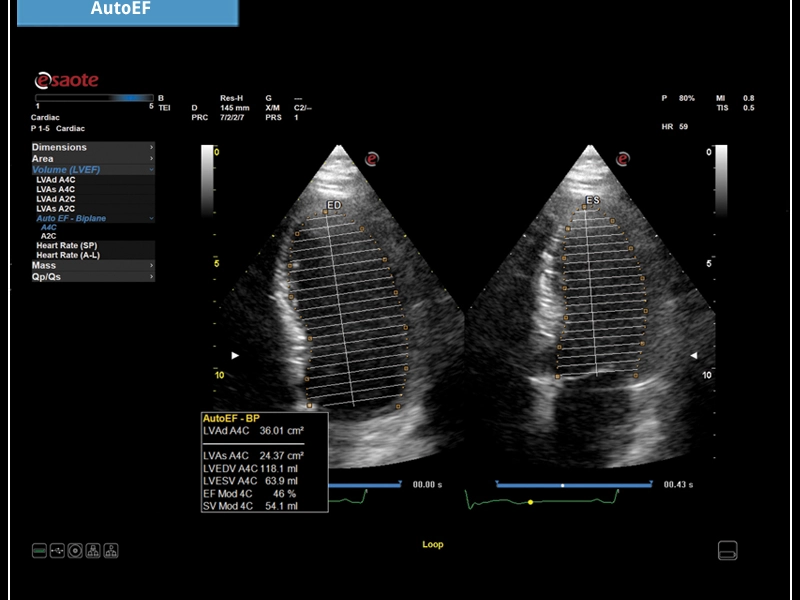

MyLab™X5 is equipped with comprehensive cardiac and vascular configurations. It functions as a complete system for ultrasound cardiovascular examination, and features customizable measurements and reporting.

General Imaging Cardiovascular